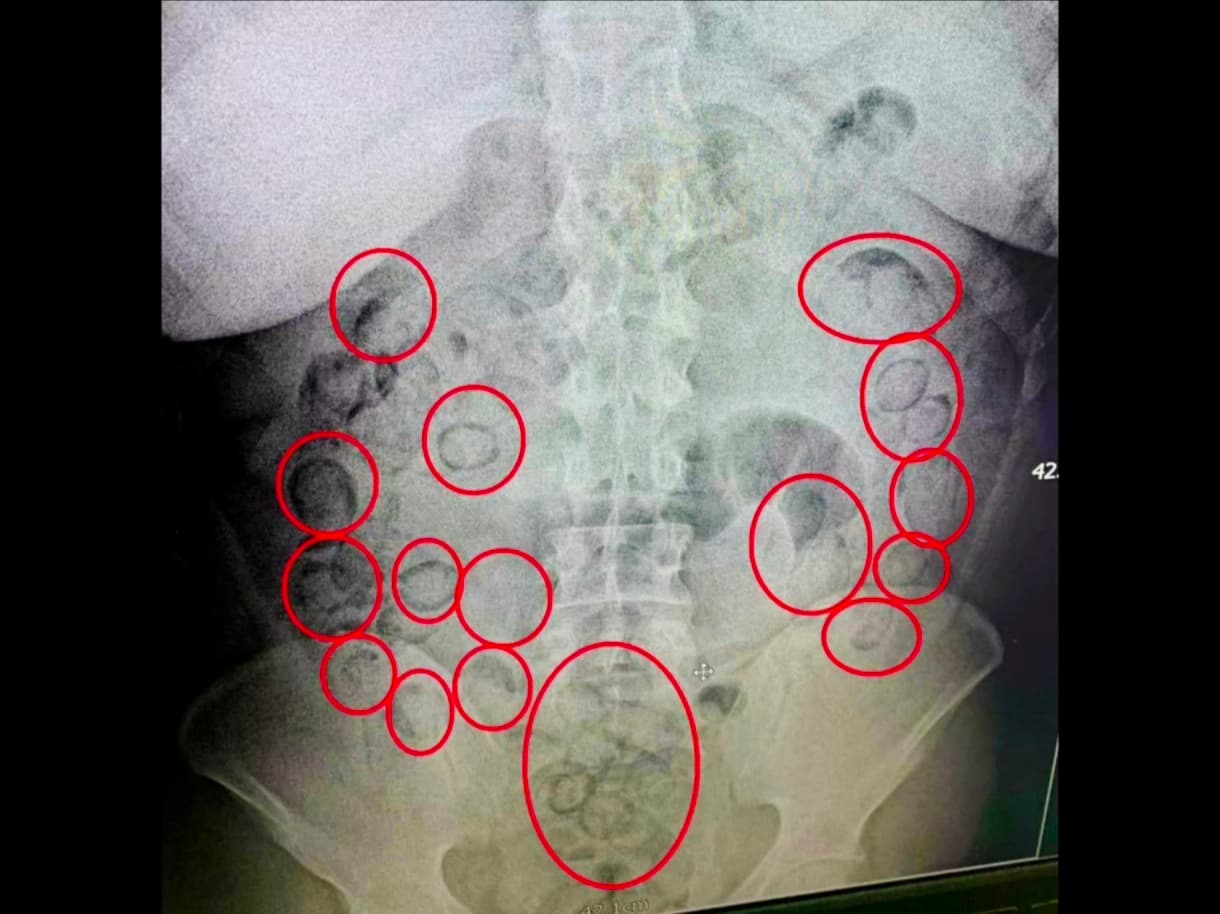

Türkiye: Polis, midesinde 433 gram uyuşturucu taşıyan bir genci yakaladı

İstanbul'da şüpheli bir davranış sergileyen bir adam, polis tarafından tesadüfen durduruldu ve midesinde uyuşturucu sakladığı keşfedildi!